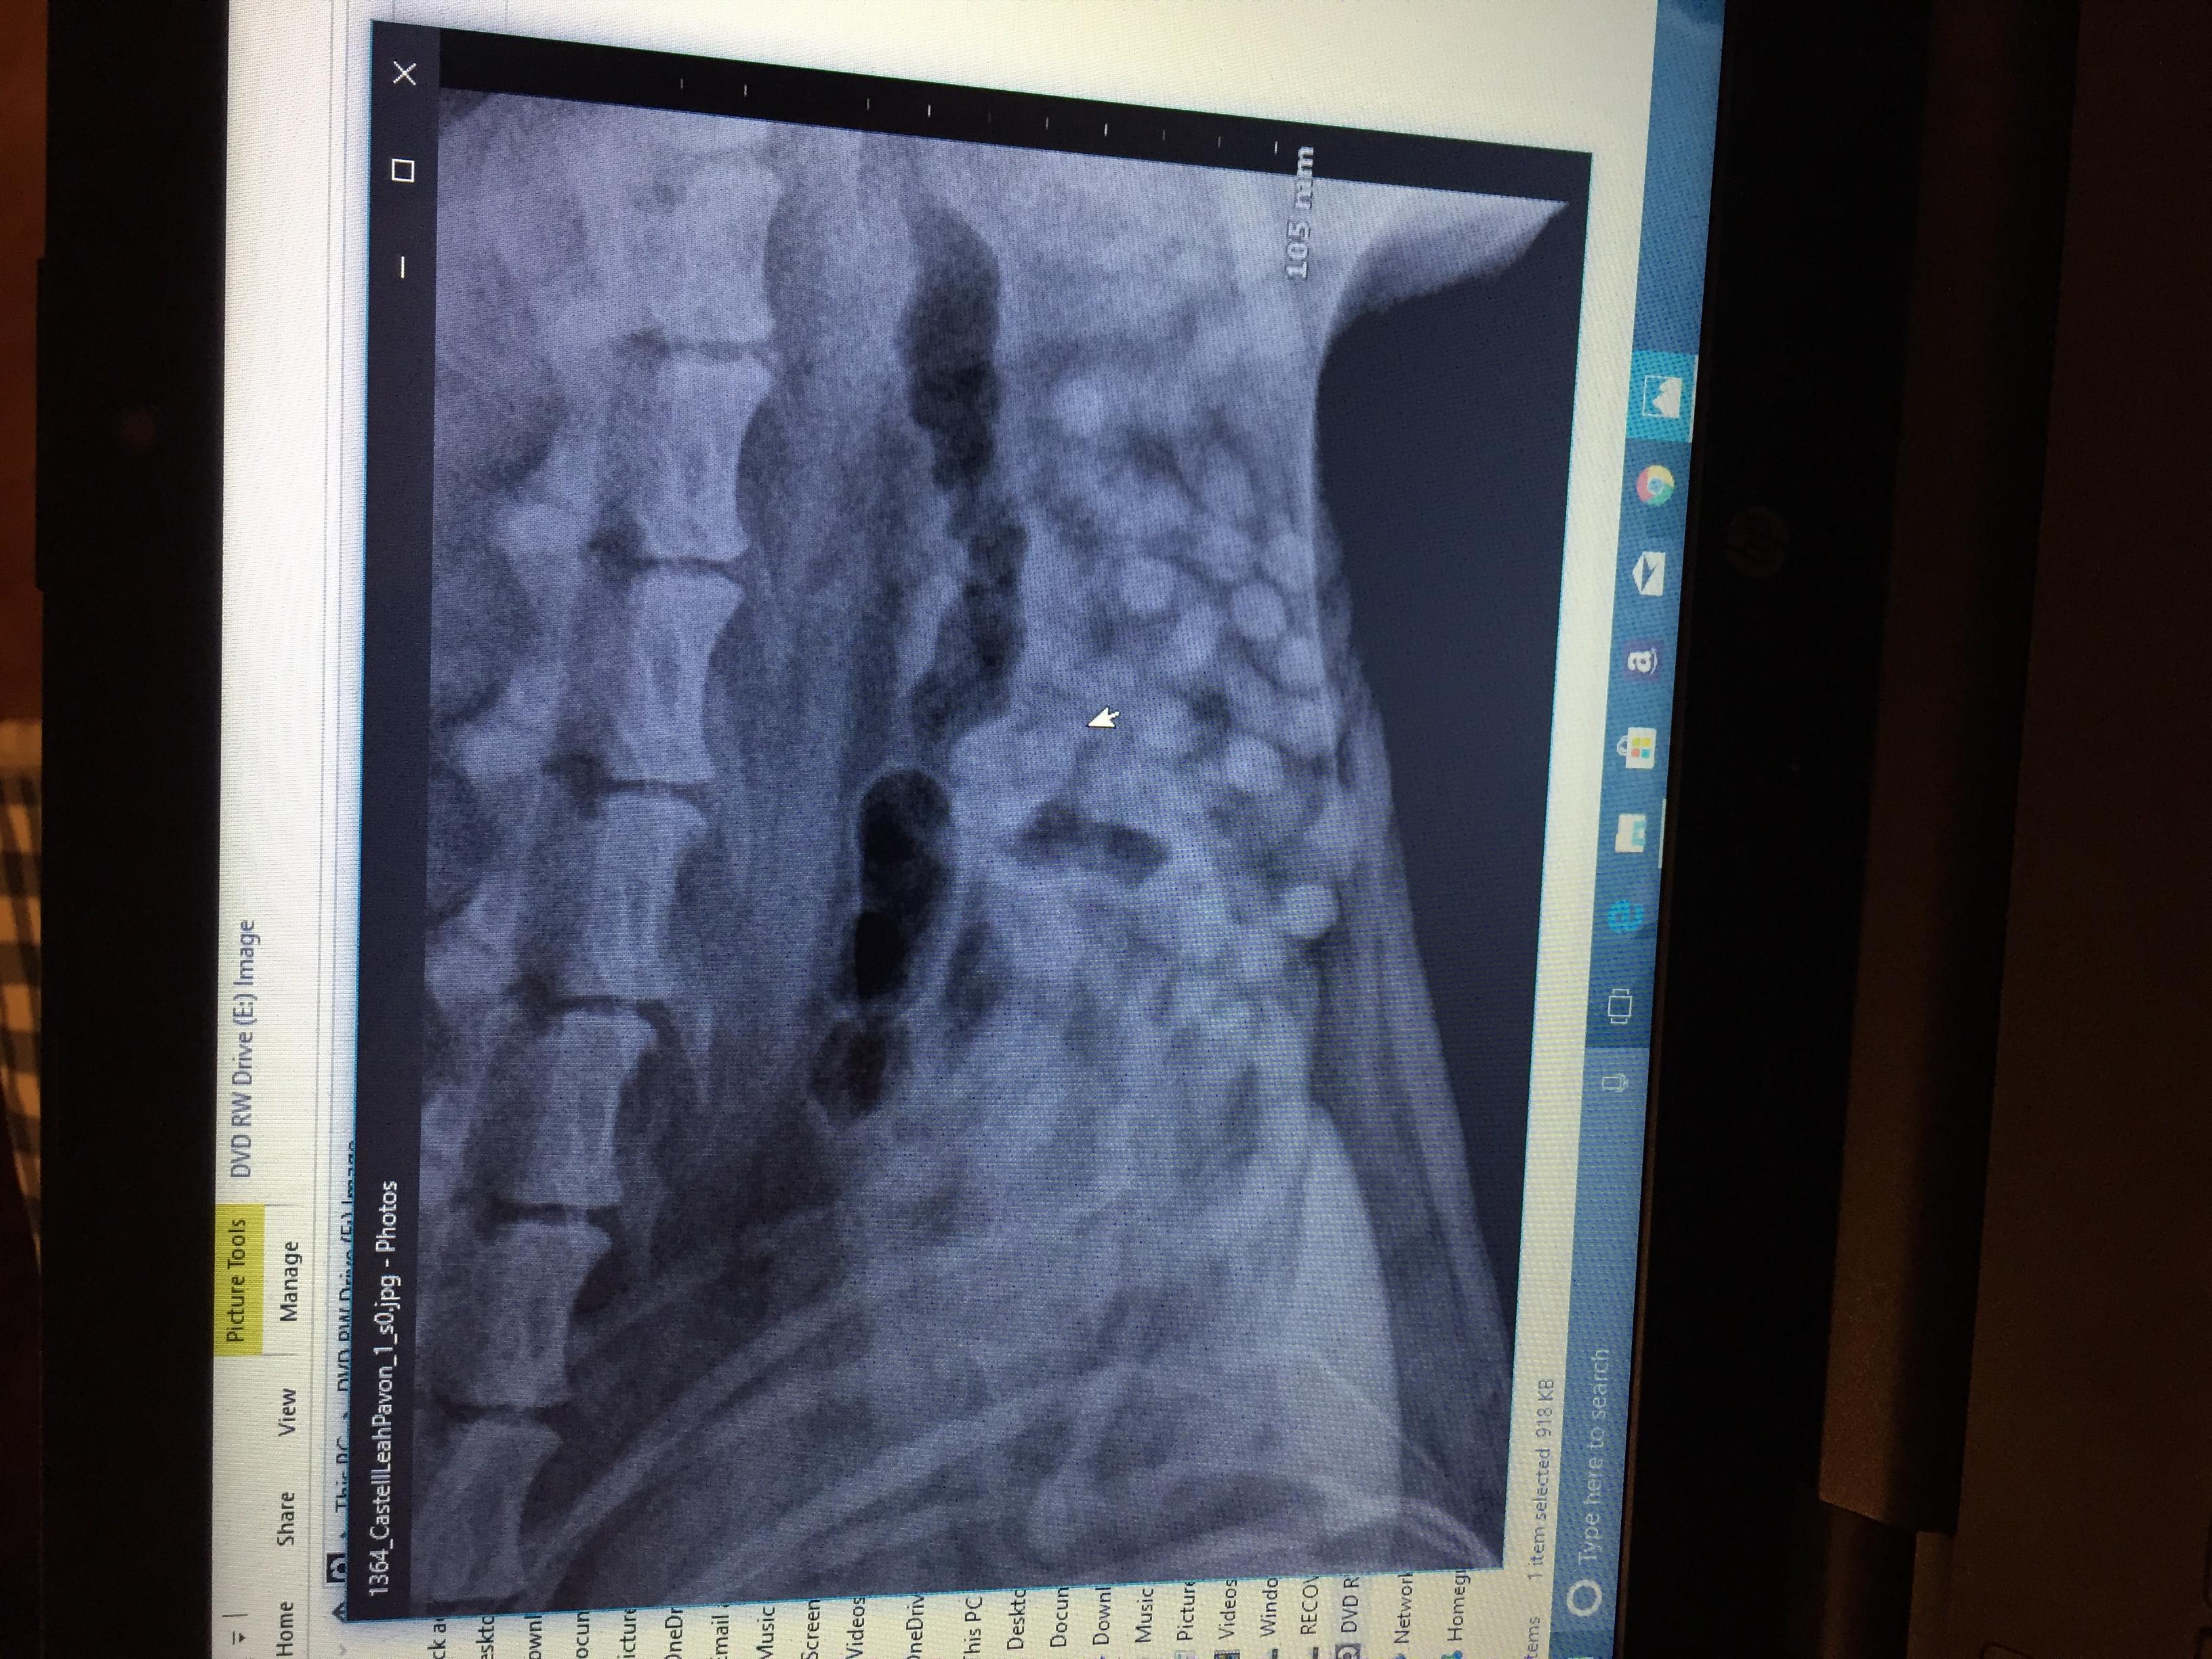

My was recently diagnosed with intestinal parasites called hook worm. the vets also did an X-ray and showed a little concern to a small area where her intestines look bunched up, they asked if she swallows things and I said she likes to eat her toys but always poops them out and I make sure of that. They didn't know what could be causing what they saw on the X-ray since it wasn't really big or obvious, my question is if these intestine parasites can do that to the intestines?

Typically, no, hookworms will not cause the intensities to become bunched. There are some parasites, specifically whipworms, that can cause an intusseception (where the bowel folds in on itself) but this usually causes severe illness (vomiting and diarrhea). Based on the X-rays, it does not look like your dog has any sort of intestinal blockage. If your dog is vomiting or having diarrhea for more than 24-48 hours after being treated for worms, then she will need to be checked out again by your vet. I hope this helps. Thanks for using Petco Pet Education Center, formerly Petcoach. Best of luck!